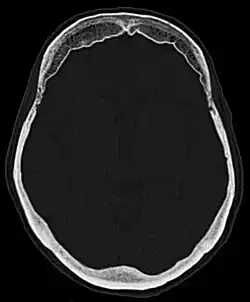

Hyperostosis frontalis interna

Die Hyperostosis frontalis interna ist eine häufige, gutartige Verdickung der Schädelkalotte im Bereich des Stirnbeins zur Innenseite hin. Die Hyperostose findet sich vornehmlich bei Frauen in und nach den Wechseljahren und bleibt in der Regel symptomlos. Meist wird sie als Zufallsbefund bei einer Röntgenaufnahme oder Computertomographie des Schädels entdeckt. Wichtig ist der Befund lediglich zur Abgrenzung eventueller Erkrankungen, siehe Differentialdiagnostik.

Die Abgrenzung in der Röntgenuntersuchung zu anderen Erkrankungen wie z. B. Knochenmetastasen oder Morbus Paget gelingt in der Regel durch die symmetrische Verteilung, die typische Ausbreitung rein frontal und nur nach innen, so wie den rein hyperostotischen und nicht destruktiven Charakter leicht.